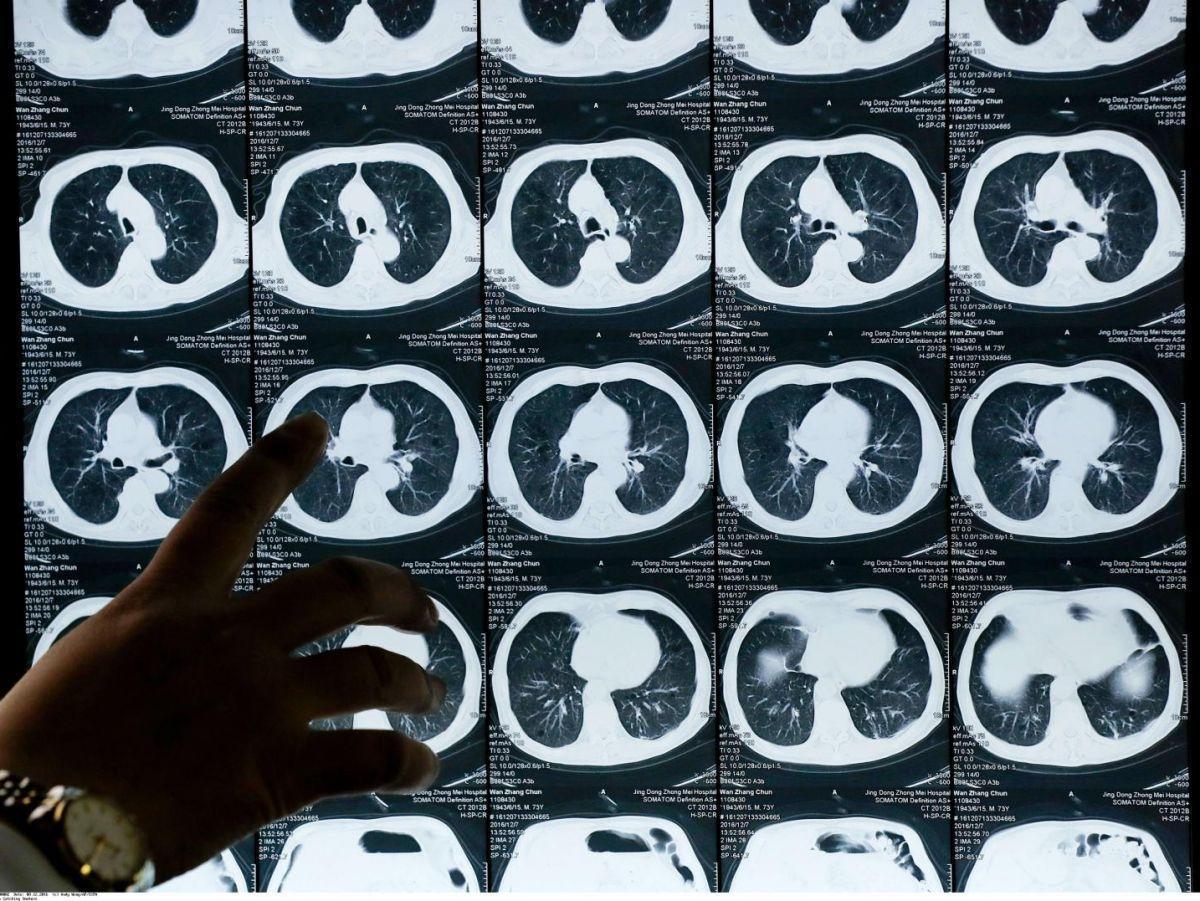

Cette annonce orale a été de plus accompagnée par une publication simultanée dans le New England Journal of Medicine, ce qui vient évidemment renforcer l’importance de son résultat. Elle concerne les patients atteints d’un cancer dit “non à petites cellules”, la forme la plus commune de ce type de cancer, présentant un type particulier de mutation, dit de type Egfr, soit environ 10 % à 25 % des patients aux États-Unis et en Europe, 30 % à 40 % en Asie.

Une fois opérés car repérés à un stade précoce, les patients inclus dans l’essai Adaura (environ 700 malades répartis dans une vingtaine de pays) ont été divisés en deux groupes.